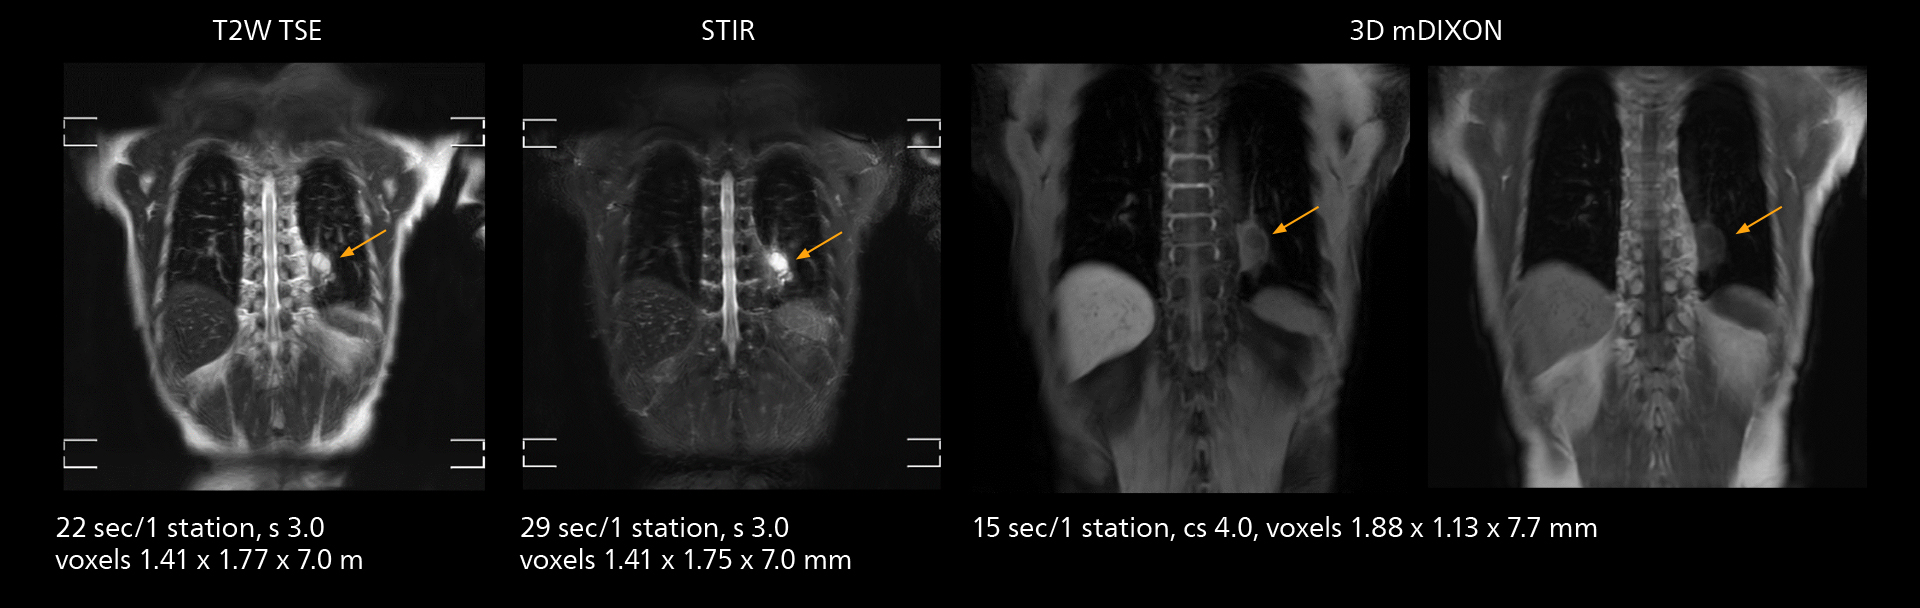

Fast whole body DWIBS examination

With SmartPath to Elition X the team can obtain excellent quality DWIBS imaging and reduce imaging time. Other sequences also fit in the examination slot. This case shows left paravertebral neurogenic tumor and Th10 vertebral hemangiomas.

The value of the Elition X gradients is also evident in DWIBS studies. “The fact that we can consistently obtain distortion‐free DWIBS while reducing imaging time at three coronal stations is excellent,” Dr. Makuuchi says. “In these patients, it’s also important that the application of Compressed SENSE to T2‐weighted, STIR and mDIXON sequences has no impact on the examination time of whole‐body imaging. As a result of the increased speed and higher image quality we realize, DWIBS studies have now become routine examinations.”